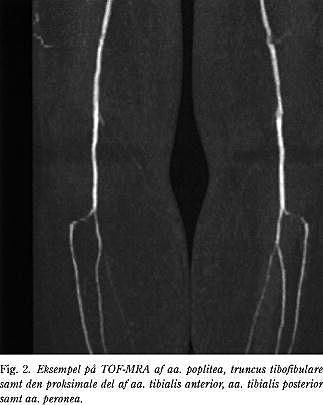

MRA uden kontrast (TOF-MRA)

Den ikke-kontrastforstærkede MRA-teknik er baseret på signalforskellen imellem protoner i bevægelse i karret og stationære protoner i det omgivende væv. Den foretrukne MRA-teknik er den såkaldte time-of-flight-teknik (TOF-MRA) (Fig. 2). På grund af tidsforbruget og risikoen for artefakter har metoden dog aldrig vundet større udbredelse forud for arterielle rekonstruktioner, udtagen i enkelte karkirurgiske centre (2, 5). Artefakter ses specielt i stærkt kurvede arterier, fx i iliacasegmentet, hvor artefakterne vil overdrive stenosegraden og -længden. Trifasisk flow, der er et normalt fænomen i større arterier, kan ligeledes medføre artefakter, ligesom respirationsbevægelser og tarmperistaltik. En fuldstæn- dig TOF-MRA-undersøgelse fra aorta til fod tager 1-2 timer (2).